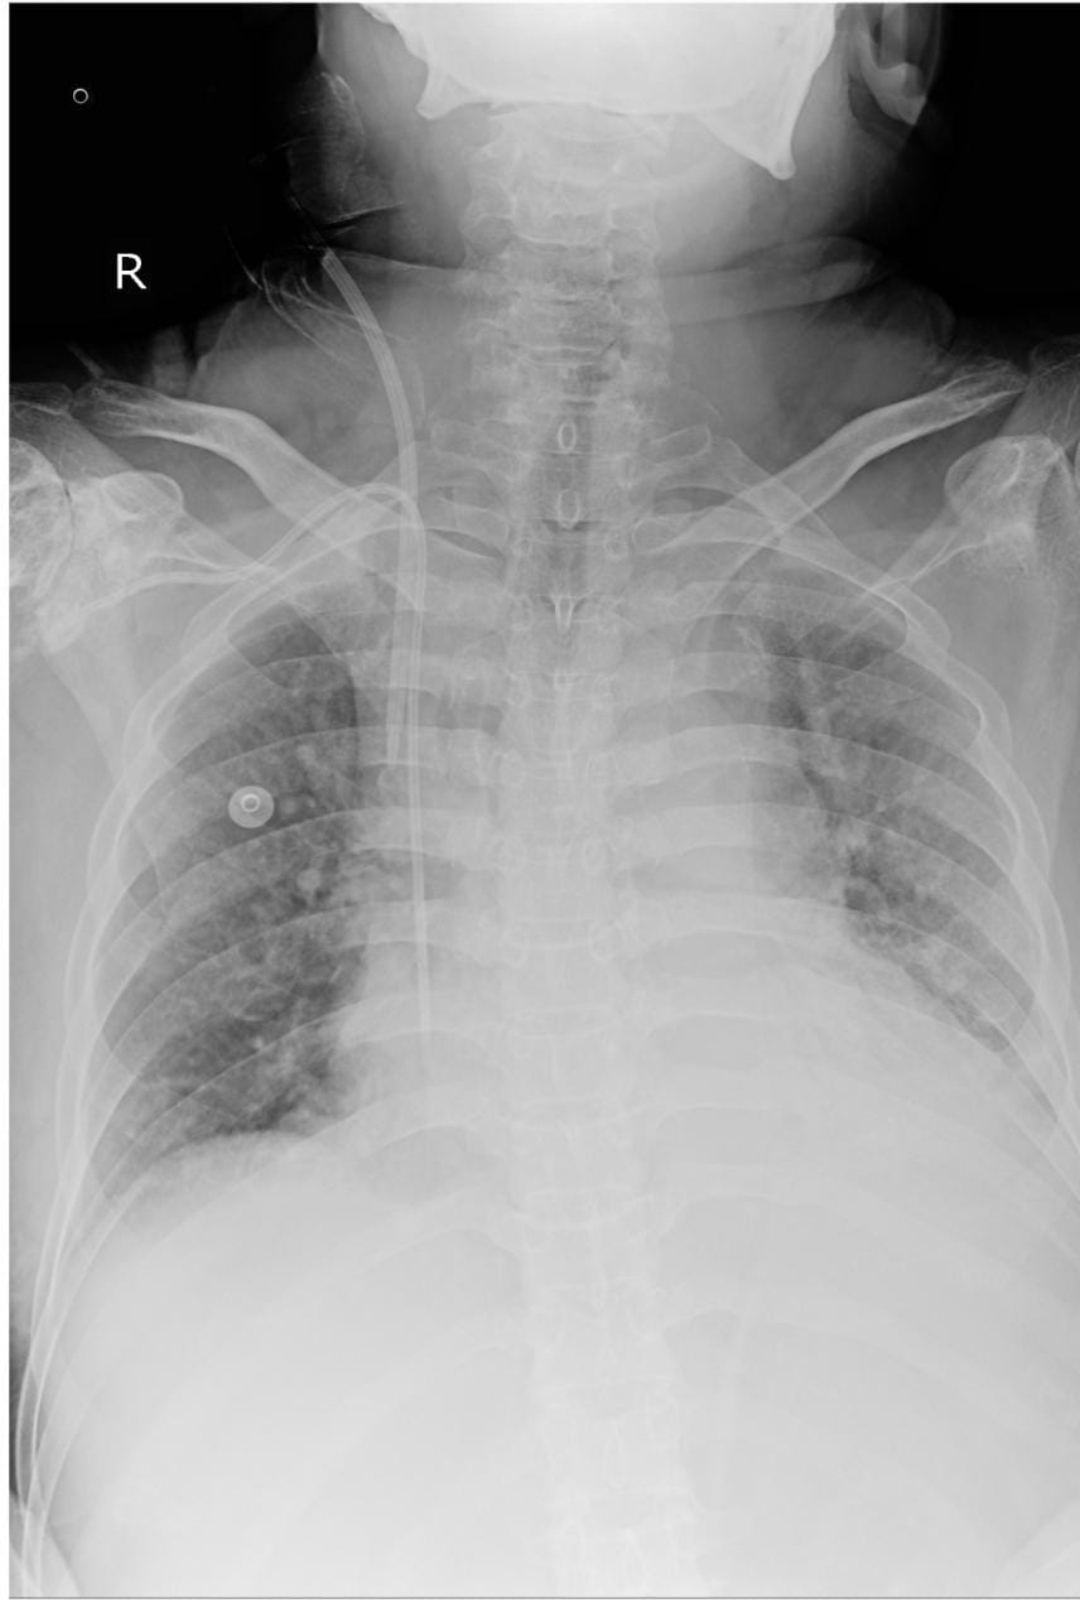

RS- BAE+,

B/L inspiratory crepts in ISA and IAA

RS-BAE+, B/L inspiratory crepts in ISA and IAA